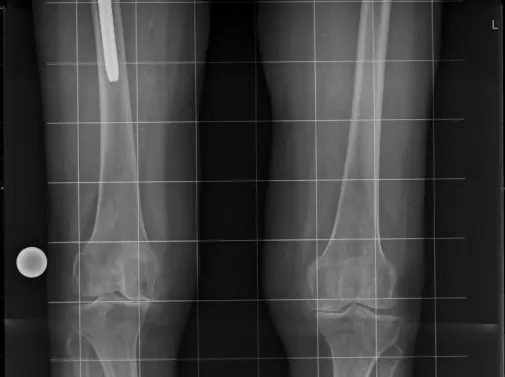

Endoproteza jest wszczepiana do zniszczonego chorobą stawu o zmniejszonej wartości biologicznej tkanki kostnej, często nieprawidłowo używanego przez wiele lat, z zaburzoną biomechaniką. Zmiany te wpływają na przebudowę i przebieg zrostu tkanki kostnej z tytanową powierzchnią implantu (osteointegracja) [19]. Wynikiem prawidłowej adaptacji kości do zmienionych warunków biomechanicznych i osteointegracji trzpienia jest bezbolesny i poprawnie funkcjonujący staw. Planowanie przedoperacyjne oparte jest na dokładnych pomiarach dokonywanych na radiogramach z użyciem specjalnych szablonów. Istotą projektowania jest uzyskanie stabilności głowy endoprotezy w panewce, odtworzenie osi obrotu stawu, zrównoważenie napięcia tkanek okołostawowych oraz prawidłowe usytuowanie kości udowej w stosunku do miednicy (tzw. offset) [20]. Widoczny w obrazie rentgenowskim pełny kontakt powierzchni endoprotezy, a w badaniach densytometrycznych zwiększona gęstość tkanki kostnej świadczą o prawidłowo umiejscowionym implancie [19, 21].